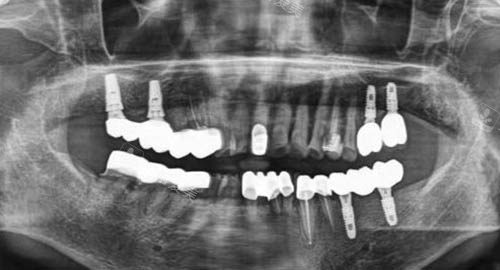

无论是常见的牙齿清洁、补牙,还是复杂的种植牙手术,他们都能熟练操作。

在种植牙方面,医生们会根据患者的口腔结构和身体状况,选择较适合的种植方案,确保种植结果的稳定性和美观性。

同时,医院还引进了较高的口腔诊疗技术和设备,如智能化口腔扫描仪、种植导航系统等,进一步提高了诊疗的更准性和可行性,让患者能够享受到高质量的口腔治疗服务。